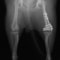

■ 症例24 キャバリア 7か月

左右膝蓋骨内方脱臼(左:グレードⅣ 右:グレードⅢ)

以前から左右後肢の跛行が認められ、整形外科学的検査・レントゲン検査により左右の膝蓋骨脱臼が認められた。症状が重度である左膝の膝蓋骨脱臼整復術を行った。外科手技は縫工筋及び内側広筋の解放、脛骨粗面の外側転位、滑車ブロック形造溝術、内外側関節方の縫縮を実施した。術後一か月時点で、左の膝蓋骨は安定しており経過は良好である。

本症例は成長期における重度の膝蓋骨脱臼であり、術後の再発の可能性もあるため、経過をしっかりと観察していく必要がある。また、今回手術を実施していない右膝に関しても経過を観察し、手術を検討していくこととする。